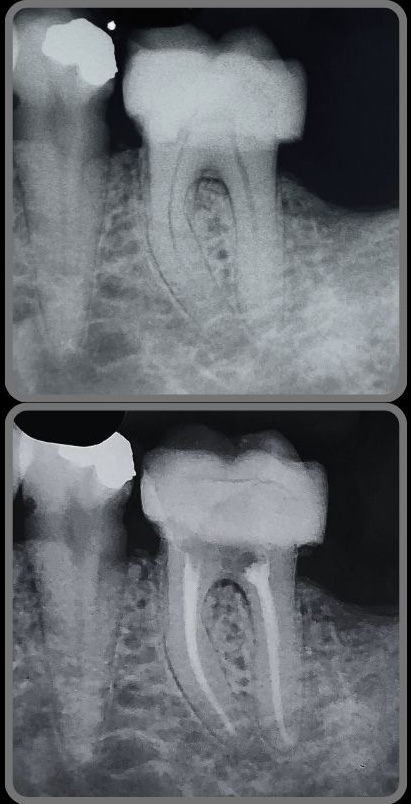

Veja alguns casos de sucesso